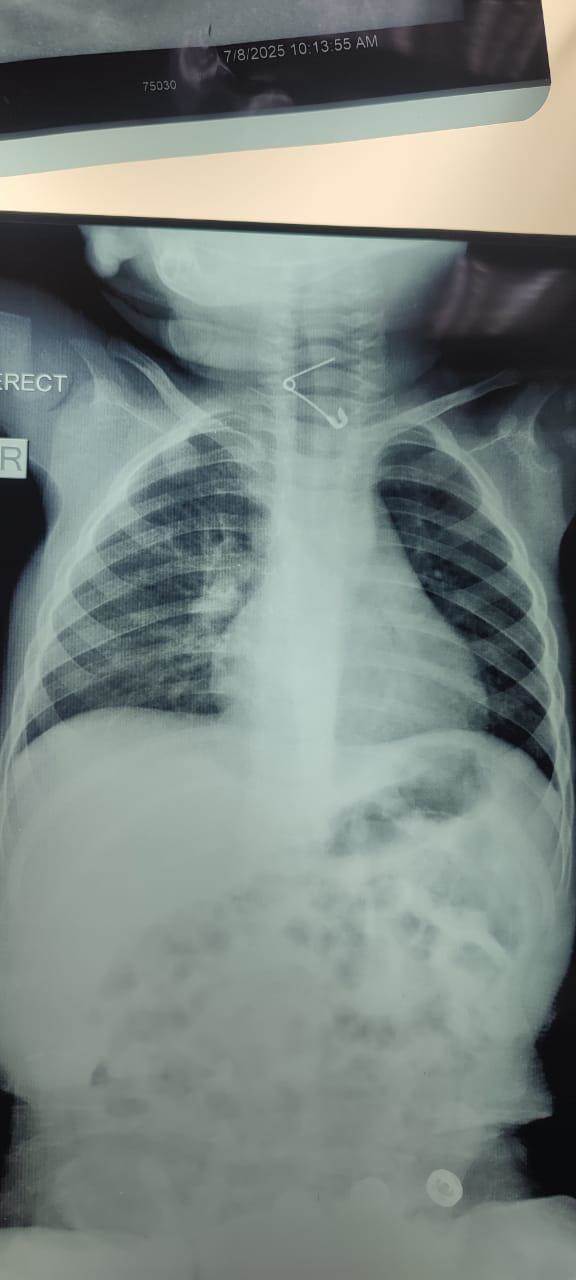

عمره عام.. إنقاذ حياة رضيع ابتلع "دبوس" بمستشفى الأطفال التخصصي ببنها

نجح فريق طبي بقسم جراحة الأطفال بمستشفى الأطفال التخصصى ببنها في محافظة القليوبية، في إنقاذ حياة طفل بلغ من العمر عامًا، ابتلع دبوسًا معدنيًا استقر في الحلق، مهددًا مسار التنفس ومسببًا خطورة بالغة على حياته.